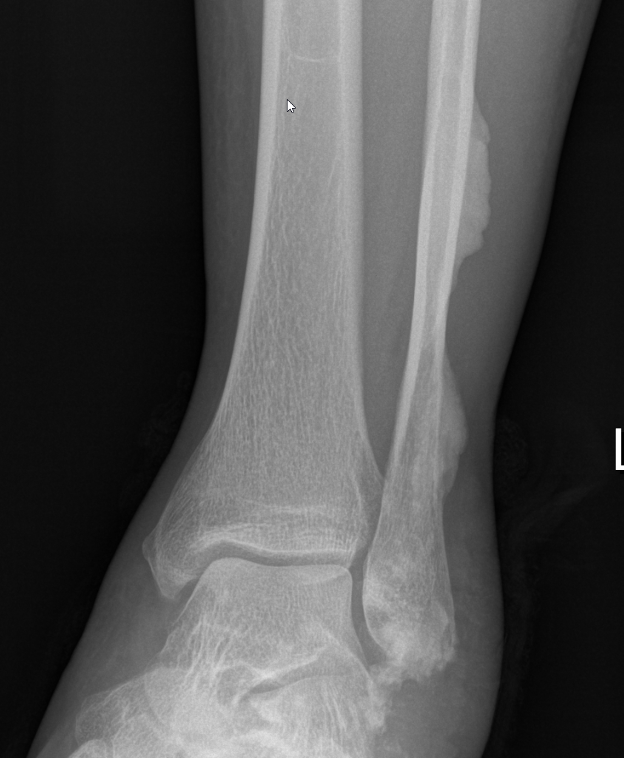

X-ray

Sclerotic lesions of bones

- undulating cortical hyperostosis

- look like wax dripping down the side of a candle